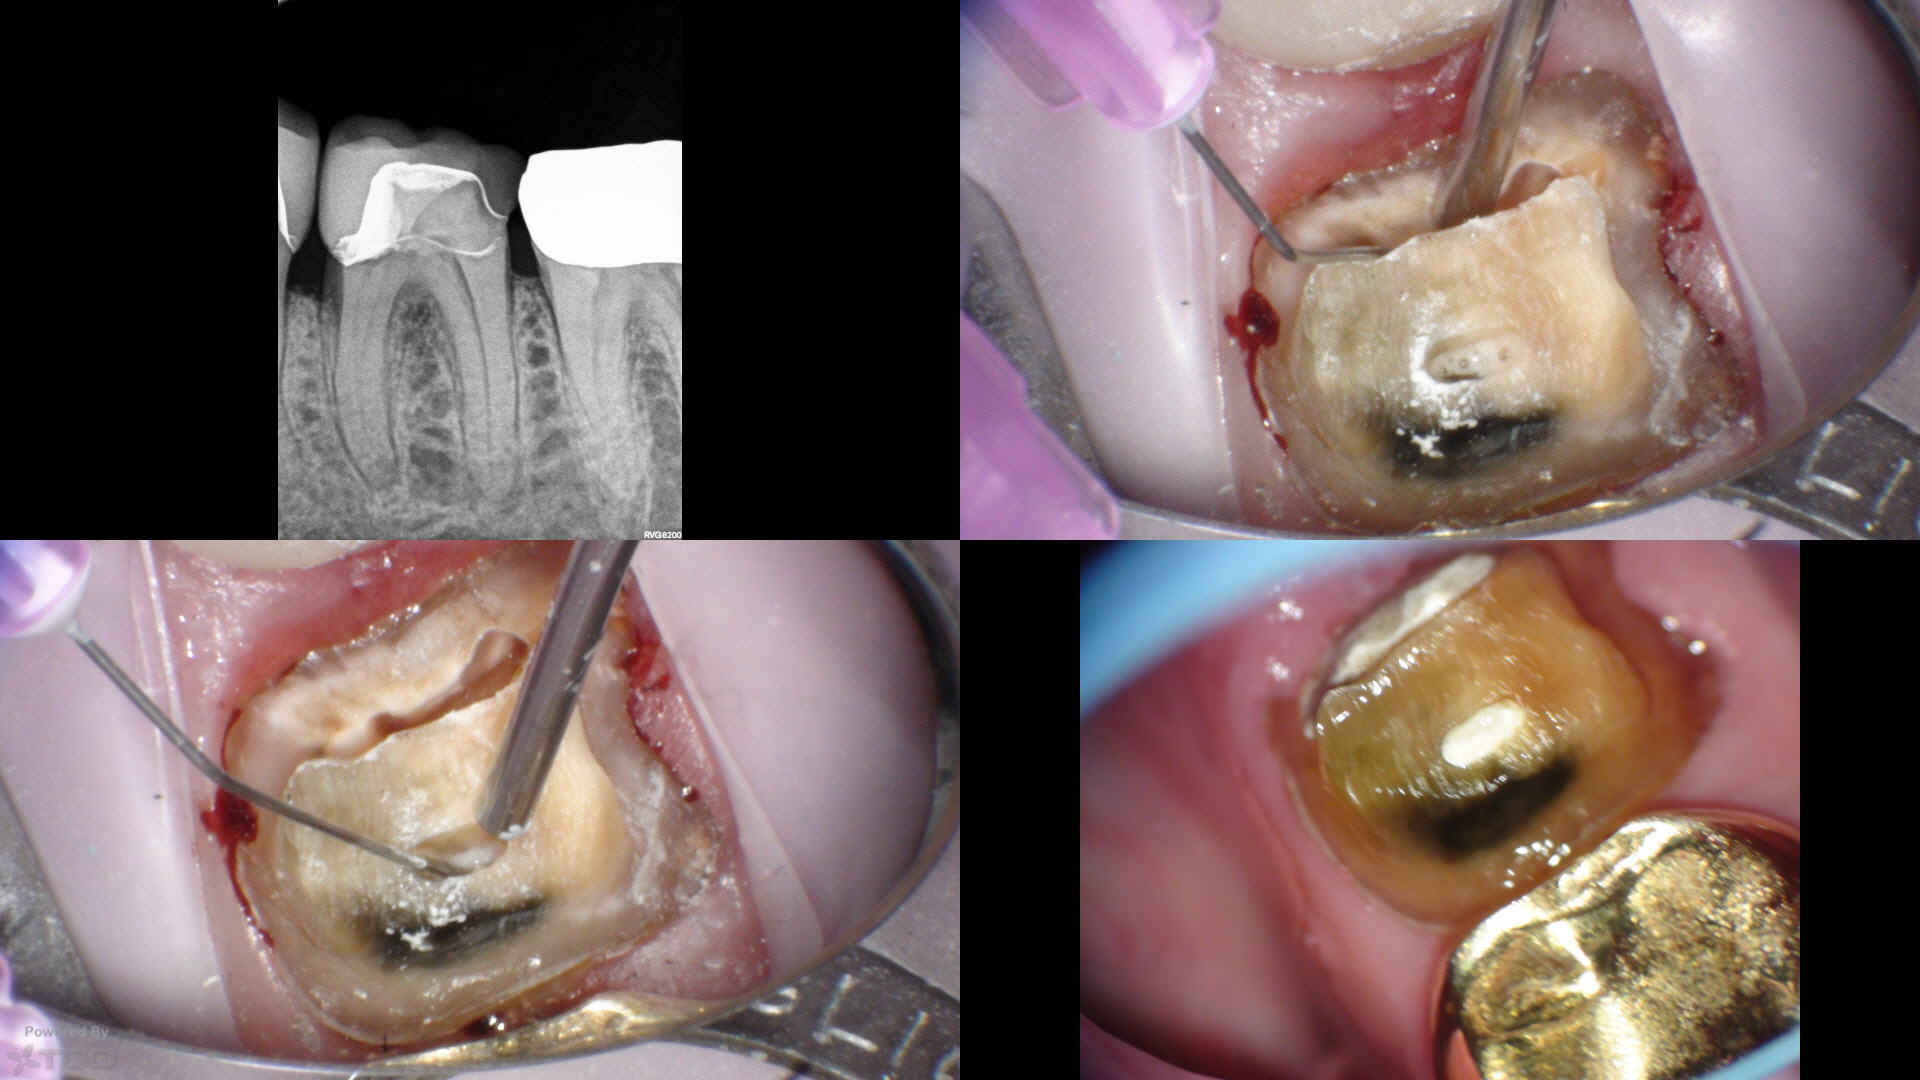

Here, traditional access would have removed most of the remaining PCD. We leveraged the caries and existing loss of tooth structure at the mesial, and poked a hole in the distal with an EG4. Chairside in the scope manages the field and NaOCl irrigation easily.

Temporary was left off with hygiene instructions. Tissue was healing well at 1wk, and was perfect today at 1mo complete (not shown). CBCT at the start visit suggested a missed DB, which was addressed at the complete visit today.

Resin mesial and distal.

Shapes were SS White V-taper 17/V.04 mesials, 20/V.06 distals.